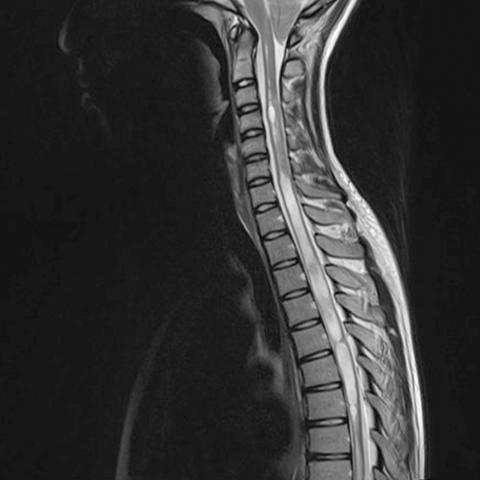

T2-vægtet MR-skanningsbillede af en patient med Arnold Chiari-­malformation og syringomyeli.

Syringomyeli kan være enten symptomatisk eller asymptomatisk. Symptomatologien varierer med hensyn til kombinationen, intensiteten og varigheden af symptomerne og afhænger af syrinx’ størrelse og beliggenhed. Karakteristisk for syrinx med central vækst er involvering af tractus spinothalamicus med segmentalt tab af smerte- og temperatursans, men bevarelse af berørings- og vibrationssans samt proprioceptiv sans. Endvidere udvikles der hyppigt smerter, paræstesier, motorisk udtrætning og pareser distalt for det involverede rygmarvssegment. Der er beskrevet symptomforværring ved intratorakale trykændringer udløst af Valsalvalignende manøvrer [22]. Diagnosen stilles ved konventionel MR-skanning (Figur 1A) [22]. Syringomyeli diagnosticeres som oftest tilfældigt eller efter symptomudvikling. Når diagnosen er stillet, følges patienterne ambulant med konsekutive skanninger. Behandlingen er medicinsk og kirurgisk ved symptomatisk syringomyeli. Den medicinske behandling er rettet mod symptomerne, mens den kirurgiske behandling er rettet mod den underliggende sygdom. Den kirurgiske behandling sigter mod at korrigere det patofysiologiske CSV-flow ved at fjerne den kausale årsag, f.eks. en tumor. Korrekt behandling kan ofte hindre yderligere progression af symptomerne (Figur 1B). Symptomerne forsvinder dog sjældent trods kirurgisk behandling. Tilstanden er kompleks og varierer fra asymptomatiske til svære progredierende tilfælde. Det er ikke muligt at skelne mellem patienter i høj og lav risiko for udvikling af symptomer og svære progredierende forløb, hvorfor patienter med syringomyeli, diverse cyster og asymptomatisk hydromyeli vil kunne have stor gavn af valideret prædiktiv diagnostik med henblik på risikostratificering [2, 22, 23].